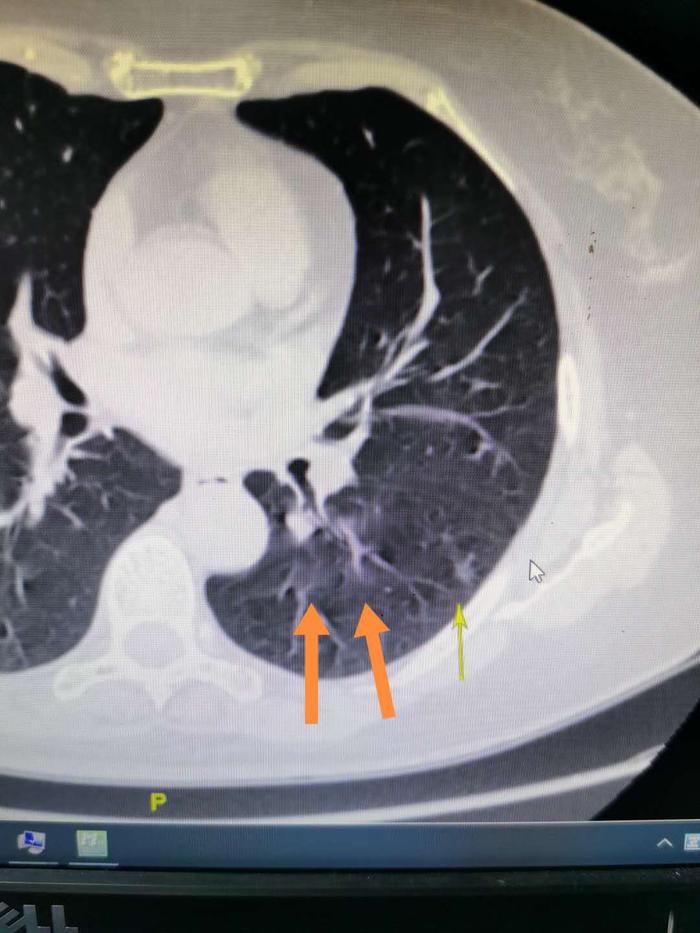

病例五、肺内差异化灌注

上图左边两个粗的橙色箭头指示的是肺内疾病稍发白的云絮状影,没有明显边界。右边细的黄色箭头指示的是一个磨玻璃结节,有明显边界,而且密度较高,看起来白一些。

肺功能不好的病人有可能整个肺到处是这种肺内差异化灌注,看起来像花斑一样。